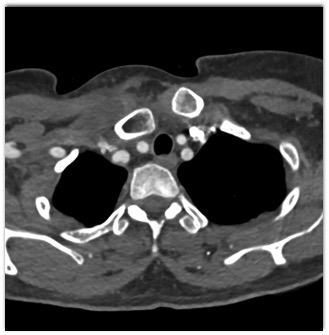

The classic dx in this patient post MVA is ?

posterior S/C dislocation